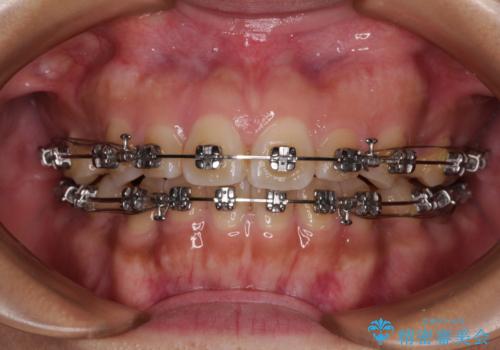

- 矯正装置

- メタルブラケット

上顎小臼歯の歯根が左右ともに大きく曲がっており、スペースクローズに時間がかかってしまいました。